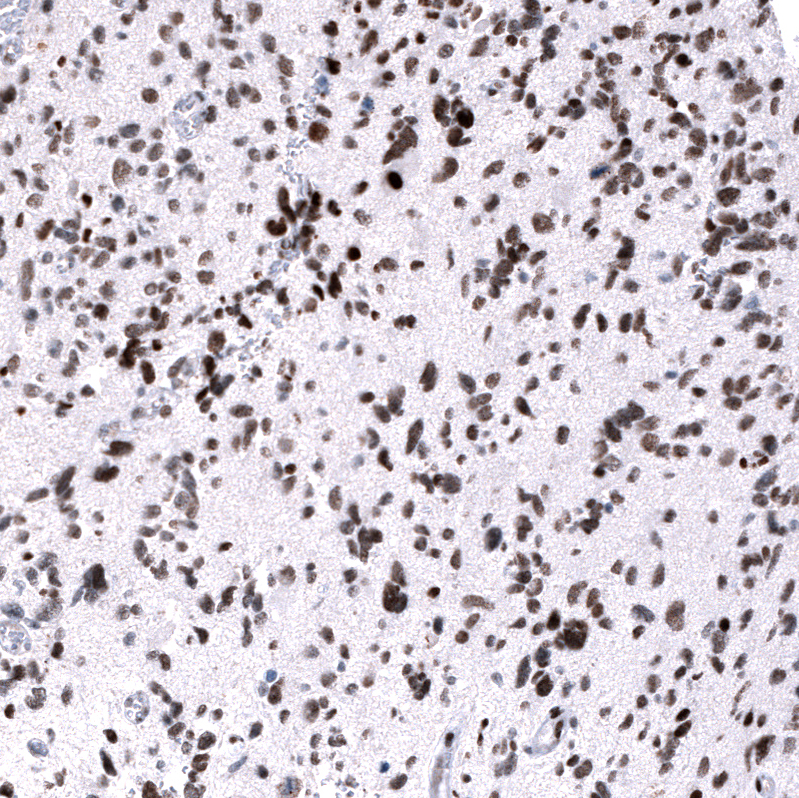

Immunohistochemistry analysis in human testis and cerebral cortex tissues using AMAb91750 antibody. Corresponding EZH2 RNA-seq data are presented for the same tissues.